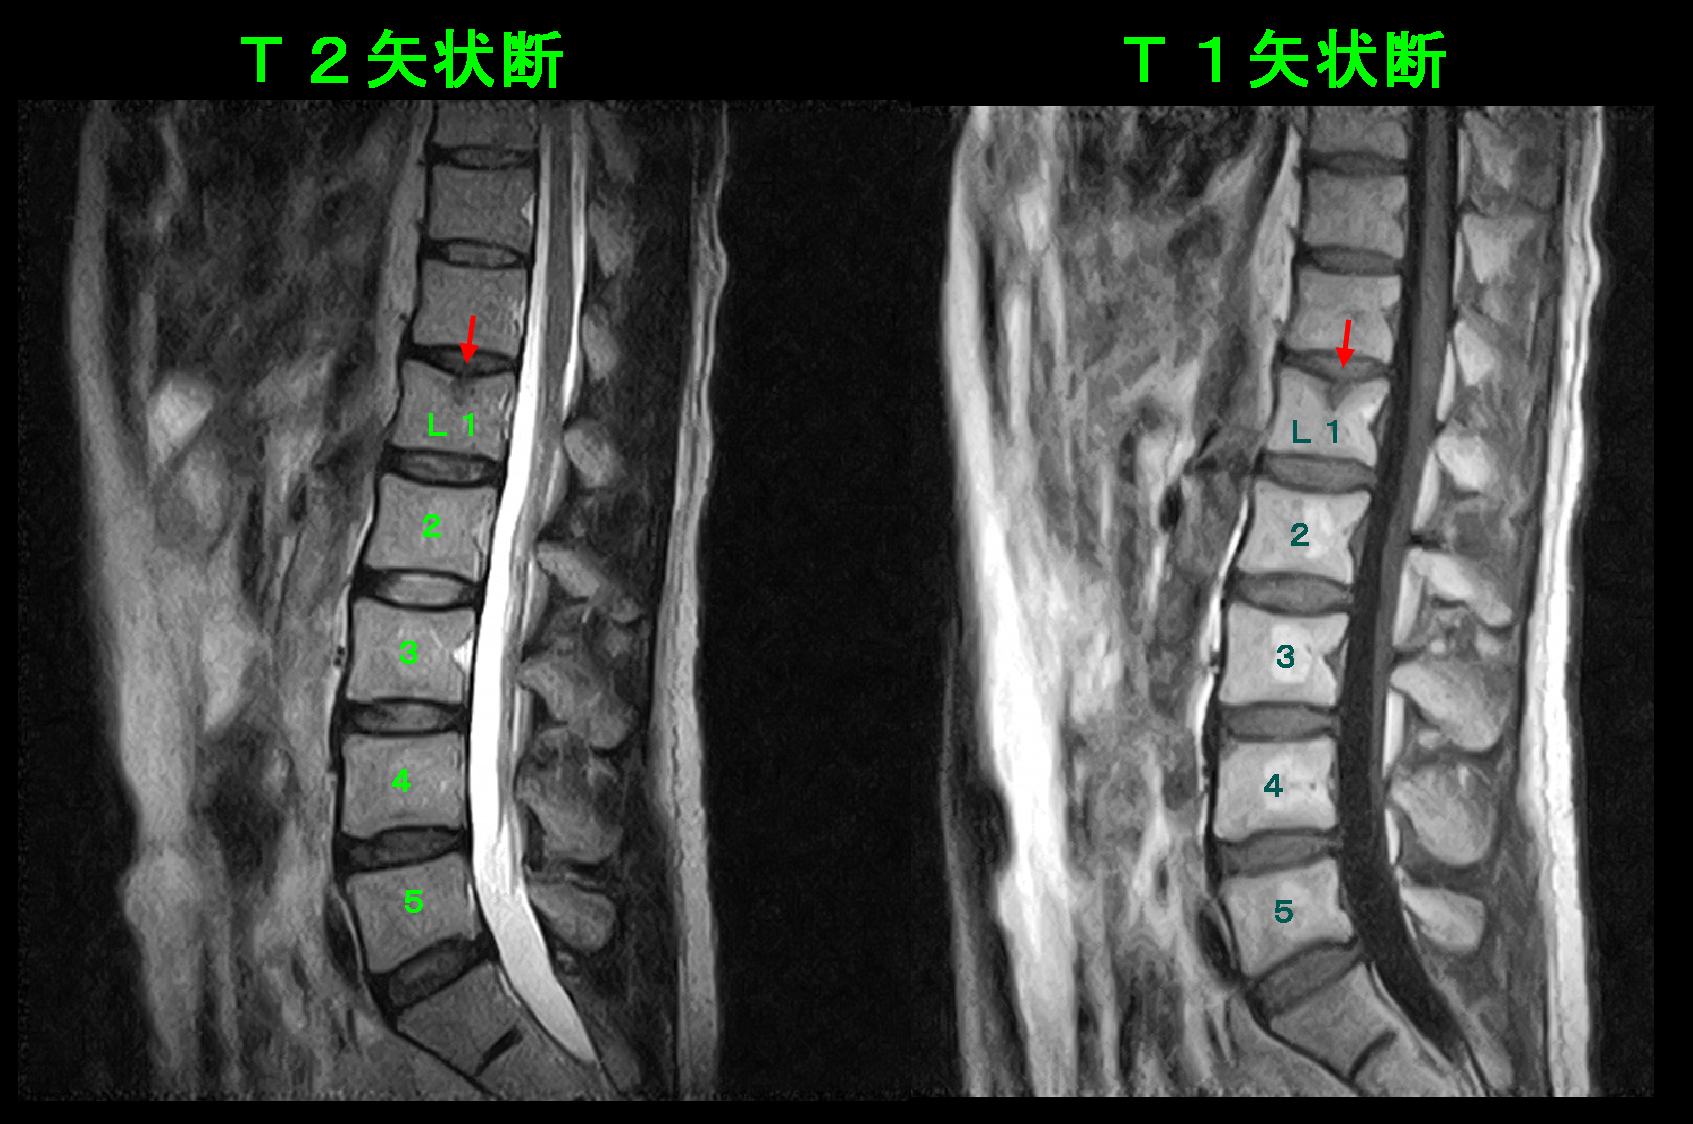

MRI検査所見では椎間板の変性と脊髄の刺激はみられず、T2矢状断でもT1矢状断でもL1椎体の上縁の中央部が黒くなっており、骨の輪郭(皮質)が軽度陥凹しています。これは錘を持った荷重負荷でL1(第1腰椎)が壊れたことにより発症した腰痛であると診断されます。鎮痛薬の処方とともに骨を丈夫にするための骨粗鬆症薬の処方も開始しました。しかし、それ以上に重要なことは安静です。安静といっても自宅で寝ていなければならないというようなことではなく、重い物は持たない、中腰、前屈の作業はしない、階段の昇降の機会をできる限り減らす、必要以上に動き回らないというような意識をもつこととなります。